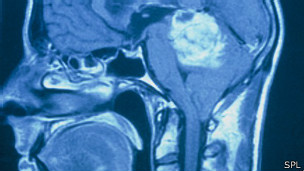

Los investigadores del estudio publicado en la revista especializadaNature Materials trabajaron con gliobastomas, un cáncer en el cerebro que es difícil de tratar y que tiene la tendencia de propagarse dentro del cerebro.

Las células cancerígenas viajan por los nervios y los vasos sanguíneos en la medida que invaden el cerebro.